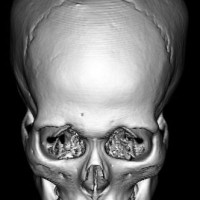

全脳照射後の頭蓋骨の部分的発育不全

2歳くらいで全脳照射を受けた子どもが15歳になりました。前頭骨だけの発育が悪くて額の間がとても狭くて,コメカミの凹みが目立つようになりました。両側の側頭部にチタンプレートを入れて額を広くして頭蓋形成をして,見栄えはとても良くなりました。このような手術を整容的頭蓋形成術といいます。